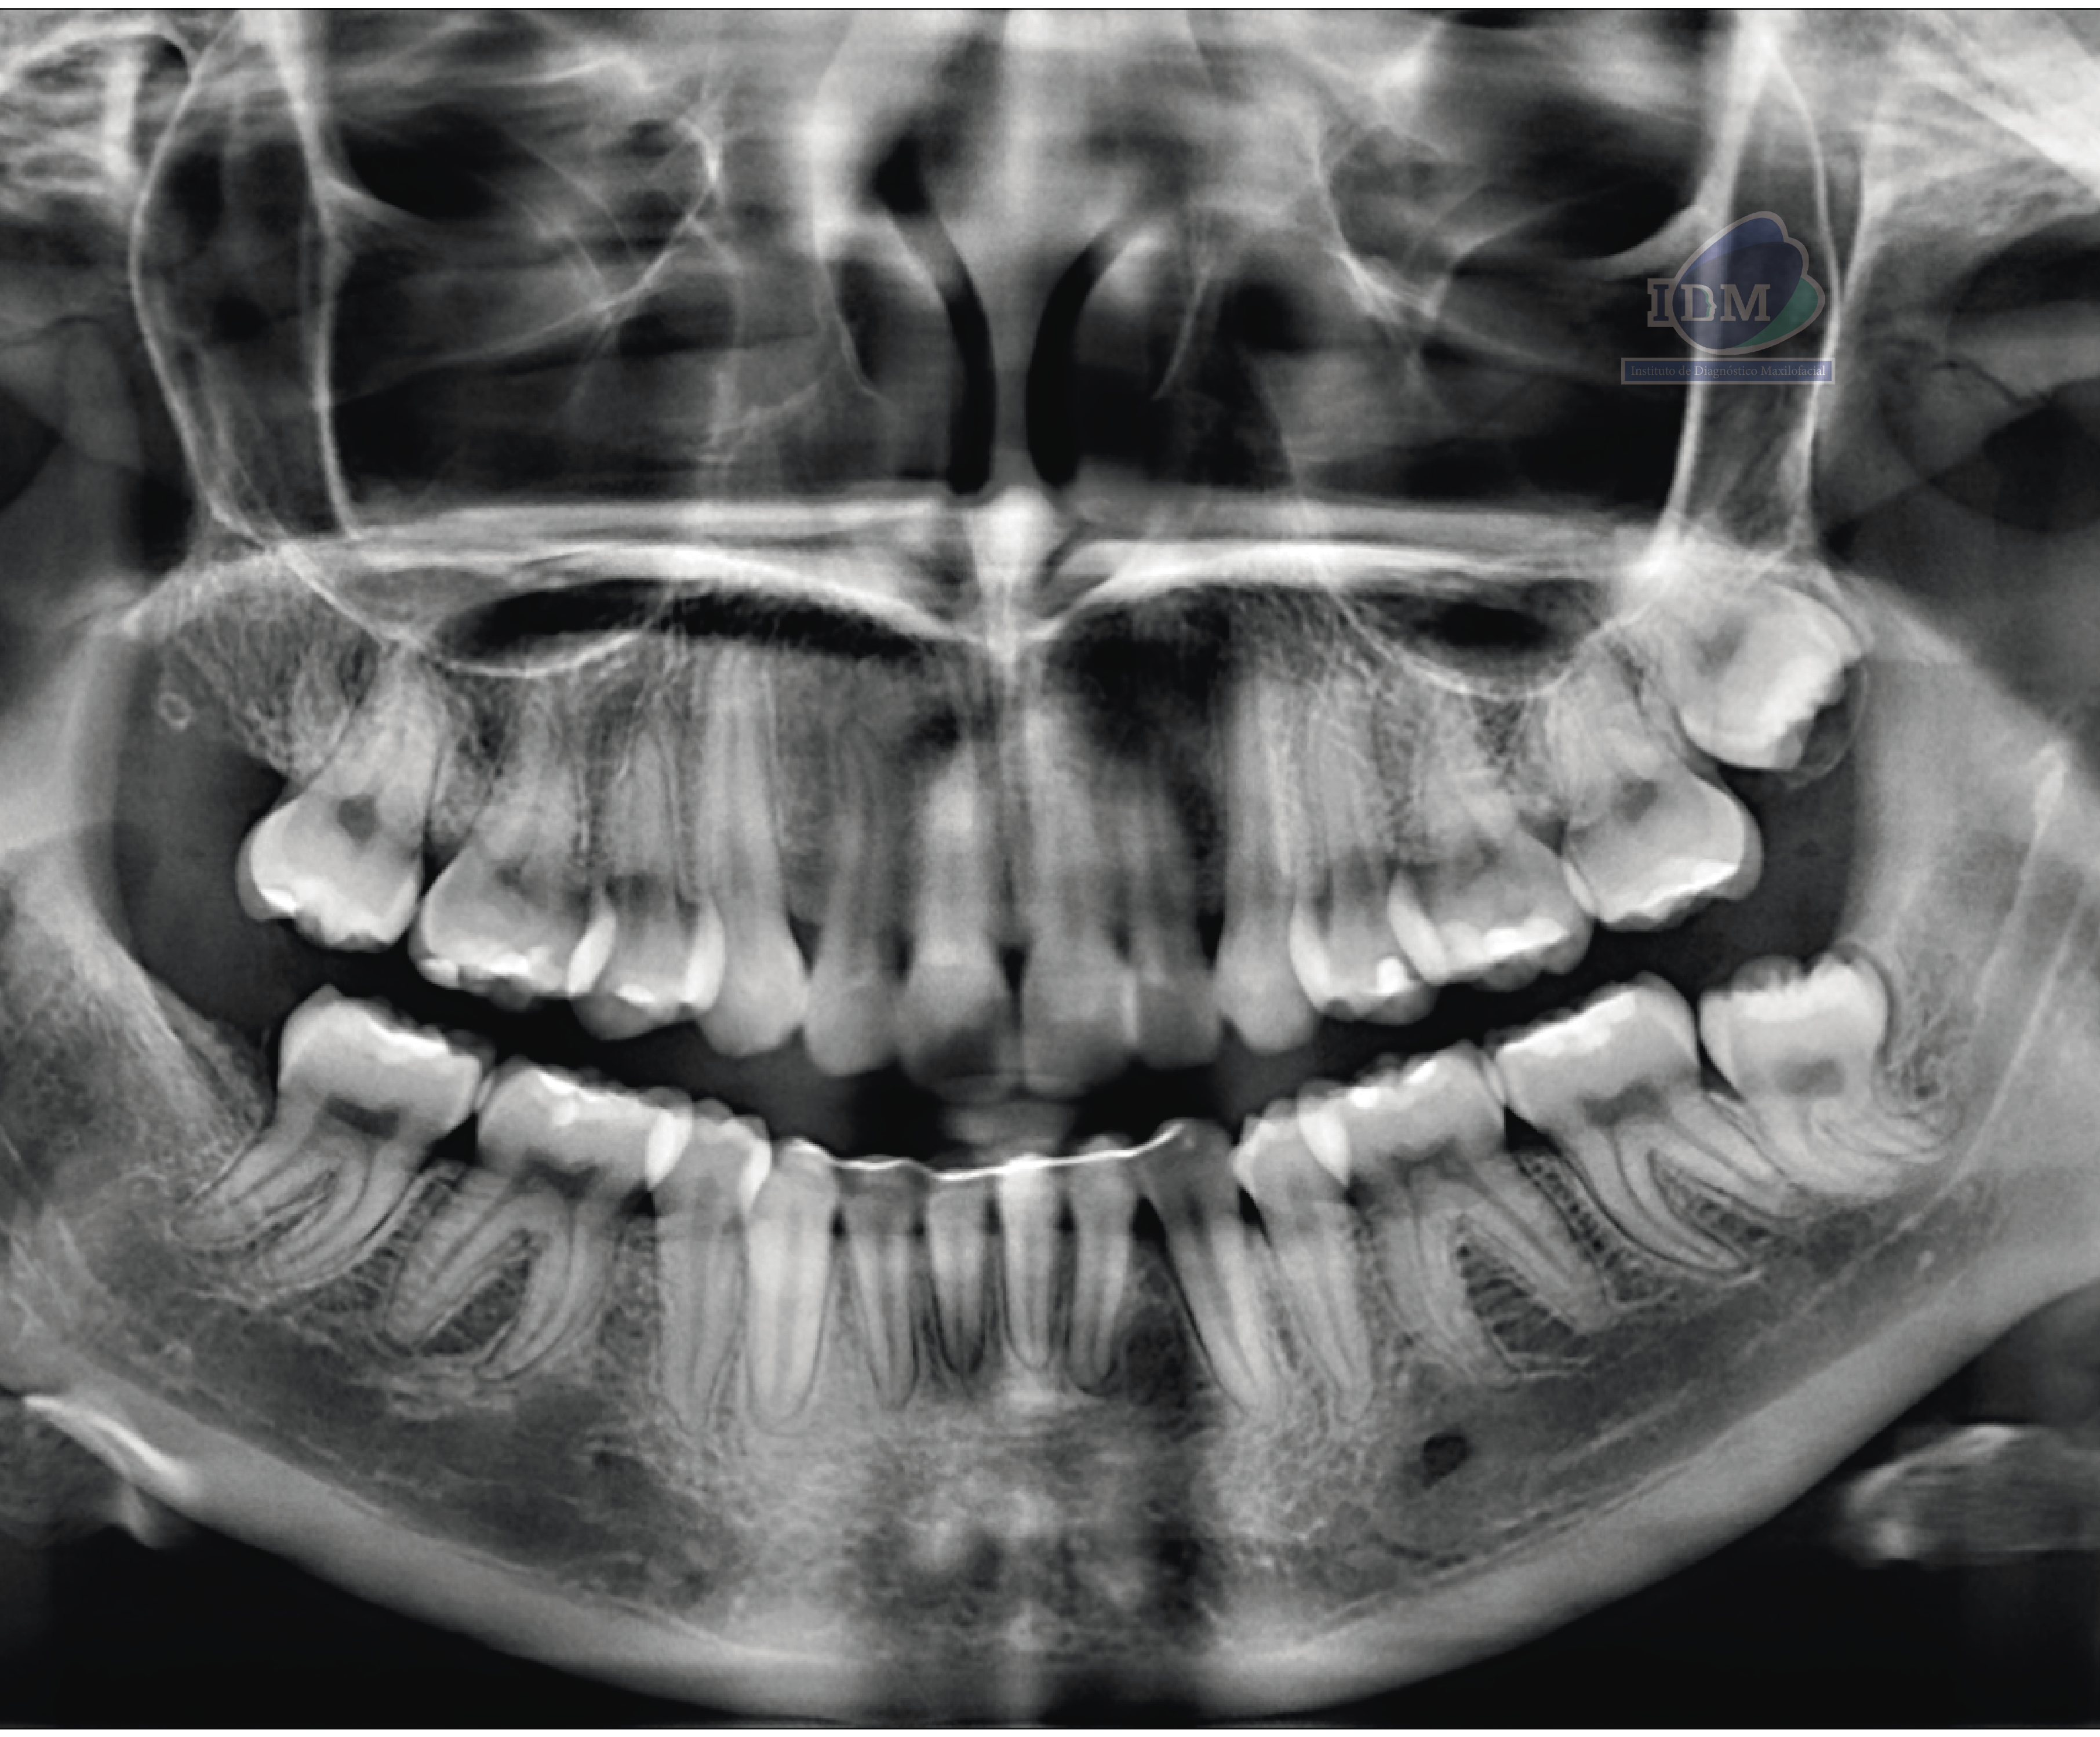

Radiografia Panorámica

Paciente femenino de 27 años acude a IDM- Sede Jesús María con motivo de consulta para control de ortodoncia y a la evaluación de la radiografía panorámica se observa neumatización de ambos senos maxilares, múltiples restauraciones coronarias, dispositivo de ferulización anteroinferior, la ausencia de las piezas 18 y 48, la retención de la pieza 28 y de la pieza 48 que a su vez presenta una raíz supernumeraria y dilaceración hacia distal.

A la evaluación de la tomografía de cráneo completo se encontró un hallazgo imagenológico en el cuarto cuadrante, se observó la bifurcación del conducto dentario inferior que iba desde su entrada por el agujero mandibular y se orienta caudal al conducto dentario principal para volver a unirse con el mismo a nivel apical de la primera molar.